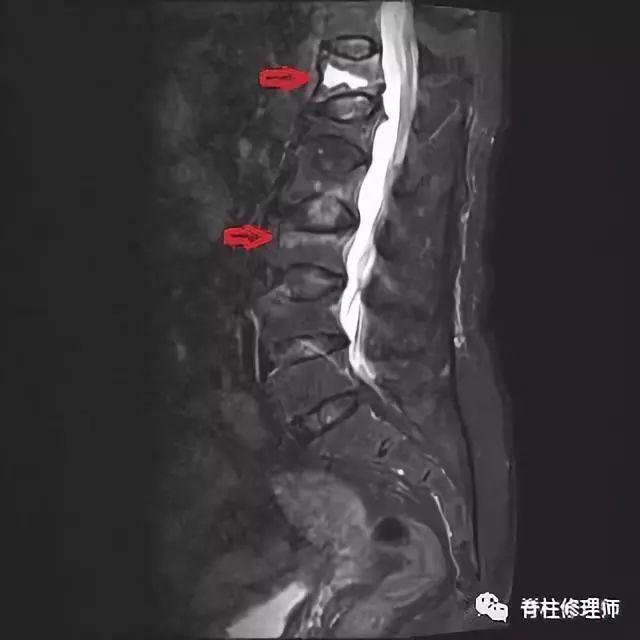

老年人常常因为没有受到外伤,发生骨折后仍不知情况,觉得腰背部不适只是衰老的表现,强忍疼痛。在椎体骨折后没有得到固定及休息,导致骨折愈合缓慢,甚至逐渐不愈合,也有发生轻微骨折不知情况后逐渐形成椎体的变形,发生kumells病。

罗湖中医院(上海中医药大学深圳医院)脊柱骨科近期就收到一位发生骨折的患者保守治疗后骨折无法愈合,发生kumells病。

对于kumells病,后凸畸形明显的患者需要行矫形手术,对于年龄较大的患者,这无疑是一道难关。